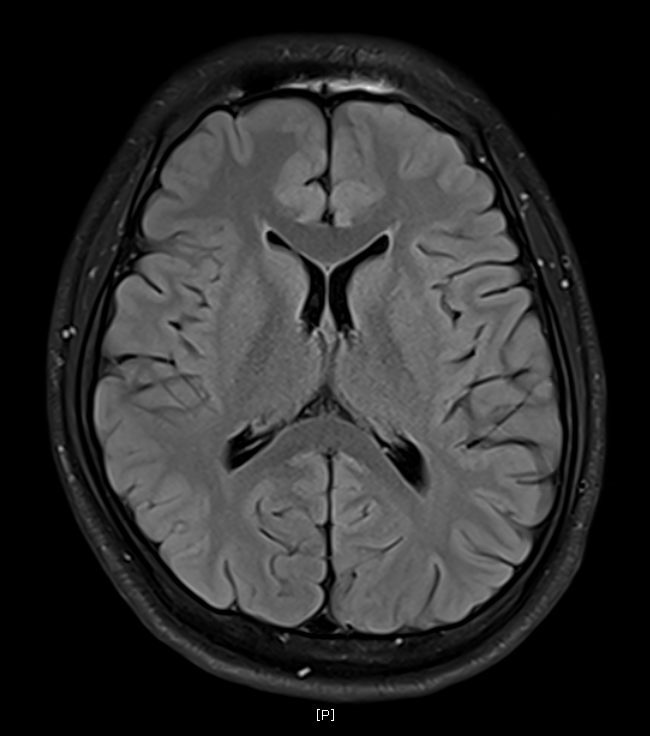

지난 금요일에 MRI를 촬영했는데요

혈관같기도 하고 하얀색 붕붕 뜨는 게 있어보이는데 (혈관같음)

한번 봐주실수 있나요? 그리고 전체적으로 괜찮은지도 봐주시면 감사하겠습니다.

특별하게 눈에 띄는 병변은 있어보이지 않습니다

말씀하신 것은 혈관의 가능성이 높겠습니다